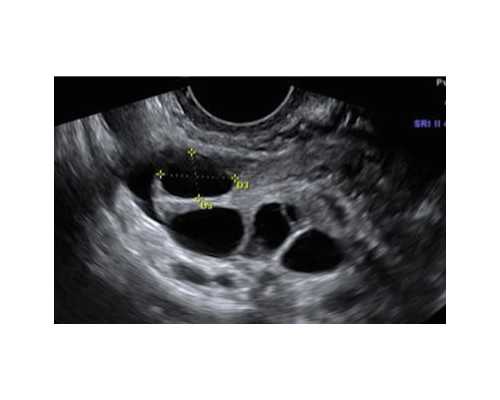

巧克力囊肿做试管前应该做的是腹腔镜,并不是宫腔镜。虽然这两种方式都属于微创治疗,但是适应症不同。宫腔镜主要用于治疗宫腔内的疾病,比如子宫黏膜下肌瘤、内膜息肉、宫腔粘连等,同时可以判断不规则出血的原因。而腹腔镜不仅可以治疗子宫的疾病,它对盆、腹腔的疾病也能同时治疗。卵巢巧克力囊肿在宫腔之外,采取腹腔镜手术创伤比较小,在去除囊肿的同时,还可以分离盆腔粘连、保护卵巢功能、促进生育,目前这是治疗卵巢巧克力囊肿的首选方式。

1、卵巢上有直径超过三厘米以上的巧克力囊肿,又或者在附件区有直径超过五厘米的良性包块